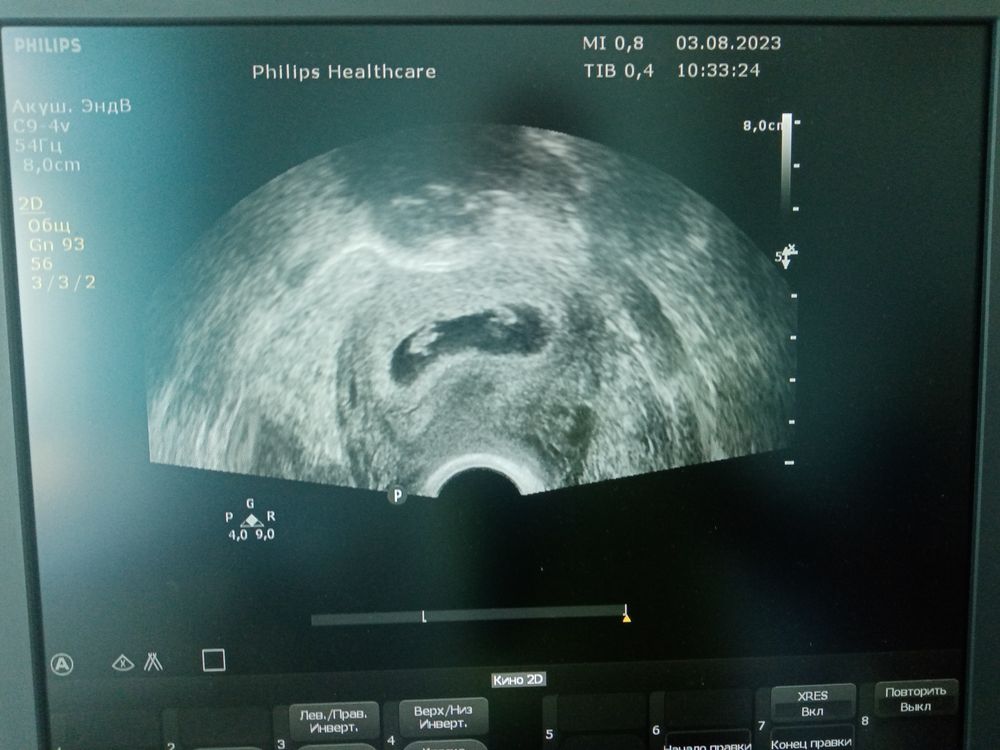

34дпп.Второе узи. Одно плодное яйцо, иии..

Изображение Вы же тоже видите??? 😍😍😍😍

Какое же чудо!!! 🤍🤍🤍✨✨✨ пусть малыши растут здоровенькими и крепенькими и родятся в срок. Поздравляю!

07.08.2023

🤩, поздравляю тихонечко 🥳почему то я подумала , что будет двое все равно , мы тогда переписывались с вами , прям чувствовалось , написали , что одно плодное яйцо , позже будет узи с серцебиением )) И вот на тебе двое малышей , здорово ❤️❤️❤️

Катёна , да, представляете?! Я не поверила своим ушам и глазам😍 это чудо не иначе! До сих пор не могу поверить и осознать, что это с нами происходит🙏🙈🙈🙈